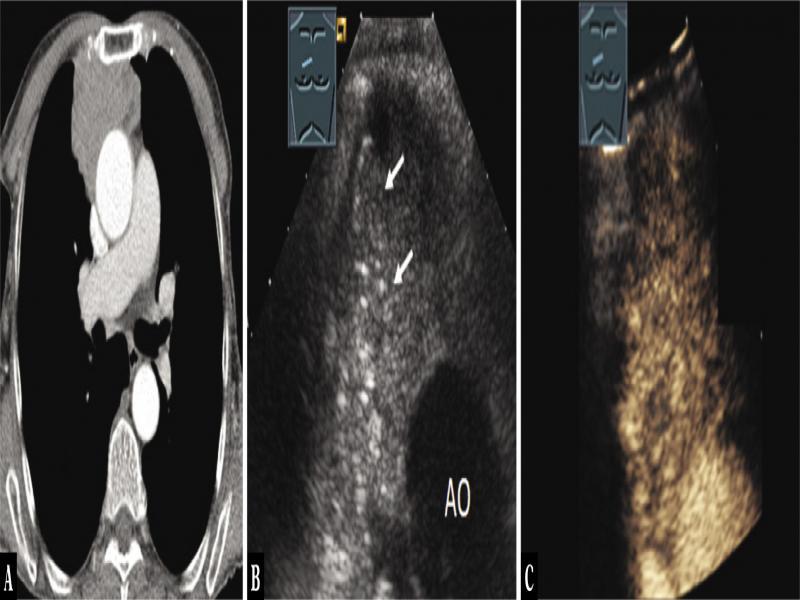

Fig. 14.

A 79-year-old female patient with a mediastinal tumor in the anterior mediastinum on computed tomography as an incidental finding (A). Thoracic ultrasound indicated a hypoechoic tumor with localized multiple small star-like reflexogenic lesions (arrows) (AO = aorta) (B); the tumor showed marked enhancement on contrast-enhanced ultrasound (C). Ultrasound-guided biopsy was performed, and the diagnosis of B2 lymphoepithelial thymic carcinoma was histologically confirmed